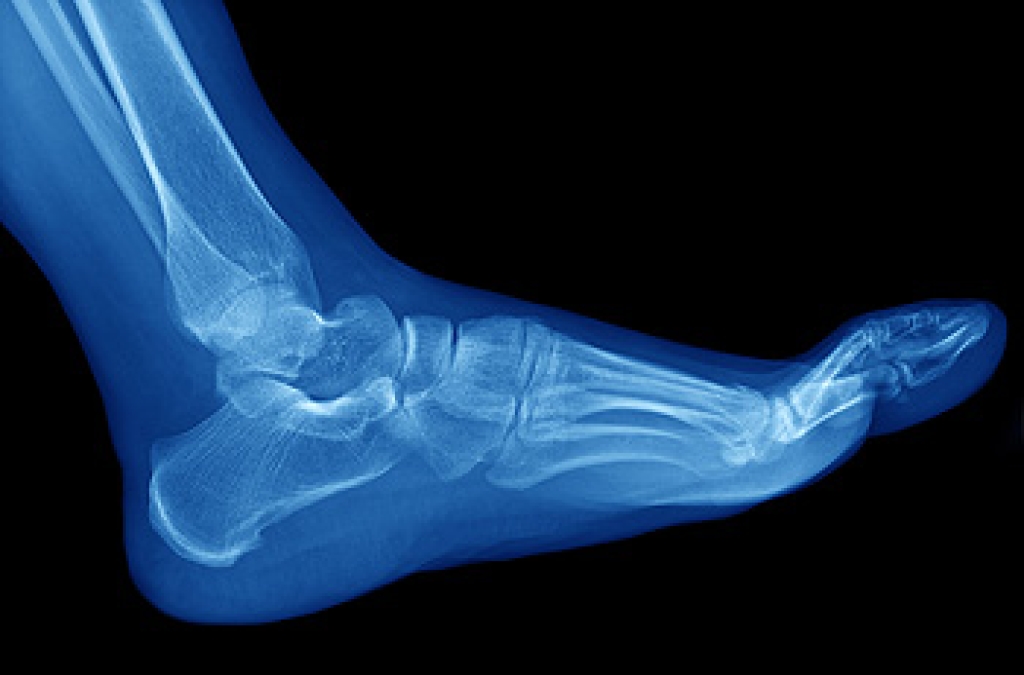

In many cases the cause of toe pain is obvious, but in others, a podiatrist may want to use more advanced methods to determine the problem. These can range from simple visual inspections and sensation tests to X-rays and MRI scans. Prior medical history, family medical history, and any recent physical traumatic events will all be taken into consideration for a proper diagnosis.

Stress fractures, those tiny cracks in the bones of the feet, are a common concern for athletes, dancers, and anyone who spends a significant amount of time on their feet. These fractures are usually a result of repetitive stress and overuse, rather than sudden trauma. One primary cause of stress fractures is overexertion, often seen in athletes who increase their training intensity too quickly. Wearing Improper footwear or a sudden change in physical activity can also put undue stress on the bones. Inadequate nutrition and underlying conditions such as osteoporosis may weaken bones, making them more susceptible to fractures. Symptoms of a stress fracture typically include localized pain, swelling, and tenderness in the affected area. The pain usually worsens with activity and eases with rest. Left untreated, stress fractures can progress to chronic pain and complications, so early intervention is essential. Understanding the causes and recognizing these symptoms allows for prompt diagnosis and proper care, reducing the risk of more severe injuries and ensuring a quicker return to an active, pain-free lifestyle. If you have developed a foot stress fracture, it is suggested that you visit a podiatrist as quickly as possible who can effectively treat this condition.

Dealing with Stress Fractures of the Foot and Ankle

Stress fractures occur in the foot and ankle when muscles in these areas weaken from too much or too little use. The feet and ankles then lose support when walking or running from the impact of the ground. Since there is no protection, the bones receive the full impact of each step. Stress on the feet can cause cracks to form in the bones, thus creating stress fractures.

Pain from the fractures occur in the area of the fractures and can be constant or intermittent. It will often cause sharp or dull pain with swelling and tenderness. Engaging in any kind of activity which involves high impact will aggravate pain.